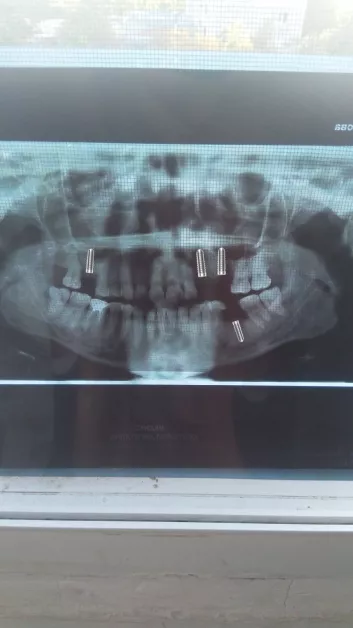

След като изчерпва възможностите за лечение в България, тя се обръща към стоматологични клиники в Турция. Оттам ѝ предлагат терапия с импланти, която може да подпомогне възстановяването на костите и тъканите в устната кухина.

Първият етап от лечението струва 2550 евро – сума, която за Милена се оказва непосилна. През последните две години разходите за пътувания, болнични престои и медицински консултации са изчерпали финансовите ѝ ресурси. Заради честите хоспитализации и силните болки само за последната година тя е загубила четири работни места.